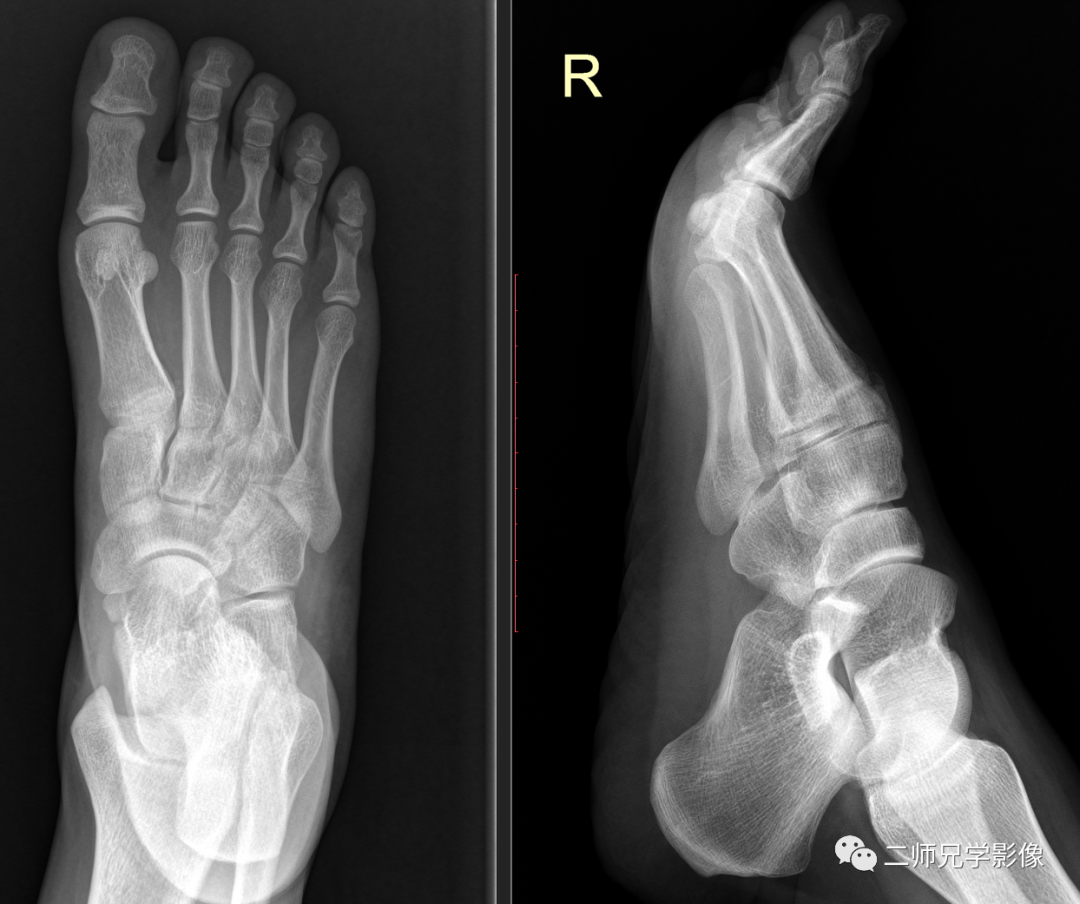

首先我们来看一个病例,临床表现:病人右足第一、二跖骨外伤疼痛,临床医生申请单开为右足正侧位。然后病人来到我们放射科进行拍片检查了。拍完过后如下图,大家有没有发现,右足侧位对第一、二跖骨显示不清,侧位片对显示第一、二跖骨效果并不好。

个人认为右足侧位对第一、二跖骨显示不清,申请单应开成右足正斜位片效果更好。